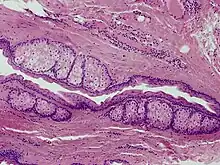

Steatocystoma multiplex is a benign, autosomal dominant congenital condition resulting in multiple cysts on a person's body. Steatocystoma simplex is the solitary counterpart to steatocystoma multiplex.[2]

The cysts are mostly small (2-20 mm) but they may be several centimetres in diameter. They tend to be soft to firm semi-translucent bumps, and contain an oily, yellow liquid. Sometimes a small central punctum can be identified and they may contain one or more hairs (eruptive vellus hair cysts). They may become inflamed and heal with scarring, like acne nodules (see nodulocystic acne and hidradenitis suppurativa).

Steatocystomas are thought to come from an abnormal lining of the passageway to the oil glands (sebaceous duct).